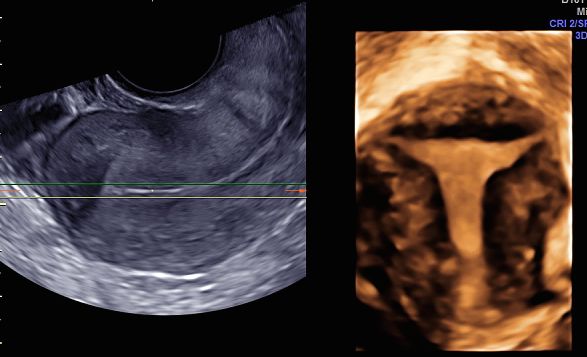

Sono esperta in ecografia 3D (tridimensionale) di cui sono stata docente a livello nazionale ed internazionale per oltre 20 aa, rivestendo incarichi nazionali nell'ambito della Società di Ecografia in Ostetricia e Ginecologia (SIEOG).

• malformazioni uterine

• setto uterino

• utero bicorne

ecografia 3D Da 260 €